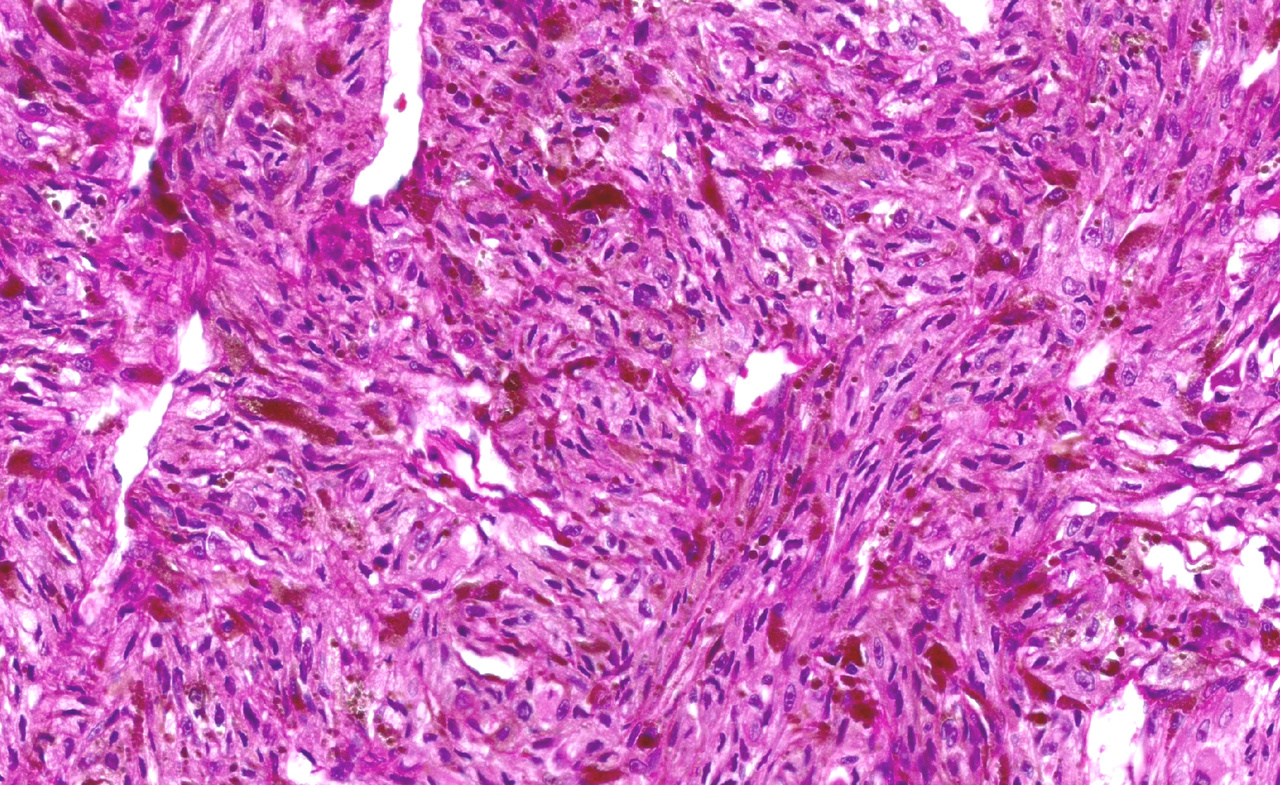

Melanomas of the uvea are the most common primary intraocular malignant tumors in adults, affecting more than 7000 individuals each year worldwide. Eventually, a large proportion of patients develop distant metastases after which median survival is about one year. Currently available treatment options for primary tumors have limited effect on patient survival.